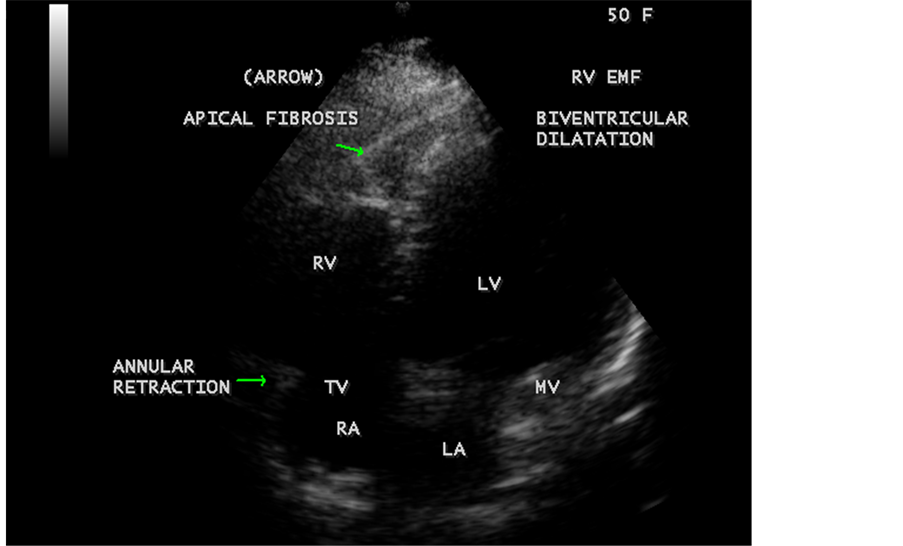

Figure 41. Endomyocardial fibrosis with biventricular enlargement in a 50-year-old female and tricuspid annular retraction.

Today echocardiography is used as the screening tool at the community level as the diagnosis of EMF could be confirmed at the bedside. Echocardiography accurately assesses the pathological abnormalities of chronic disease and it is the gold standard technique for the diagnosis of EMF [36] . It reveals dense endomyocardial echocardiograms along different parts of the mural and valvular endocardium and AV valve dysfunction [37] as shown in Figure 3 to Figure 7, Figure 10 to Figure 15, Figure 17, Figure 18, Figure 20 to Figure 75 and Figure 78 to Figure 84. The typical feature of EMF is the obliteration of trabecular portion of the ventricle and in advanced cases, there is shrinkage of the cavities creating an apical notch, regurgitation, slow flow with spontaneous echo contrast as in Figure 36 and considerable pericardial effusion. Similar to apical notch of right ventricle, a right atrial notch is well seen as contraction (or retraction) of tricuspid annulus as in Figure 41 and right atrial notch as in Figure 42 and Figure 43, indicating the retraction of right atrial cavity as a peculiar feature of right ventricular EMF. Biventricular enlargement as shown in Figure 41 and biatrial

enlargement as in Figure 33 are the characteristic features of advanced stage of EMF. The fibrosed muscular trabeculae extending into the cavities from the walls of the chambers in the right ventricle visible as “cobra heads” as in Figure 4 and in pericardial sac as in Figure 29. Aneurysmal right ventricle with scattered areas of fibrosis in the sub tricuspid region and a notch in the right atrium is well seen in a 14-year-old boy as in Figure 43. Right atrial notch is frequently noticed in EMF patients as shown in Figure 42 in a 47-year-old male with left ventricular EMF and moderate pericardial effusion.